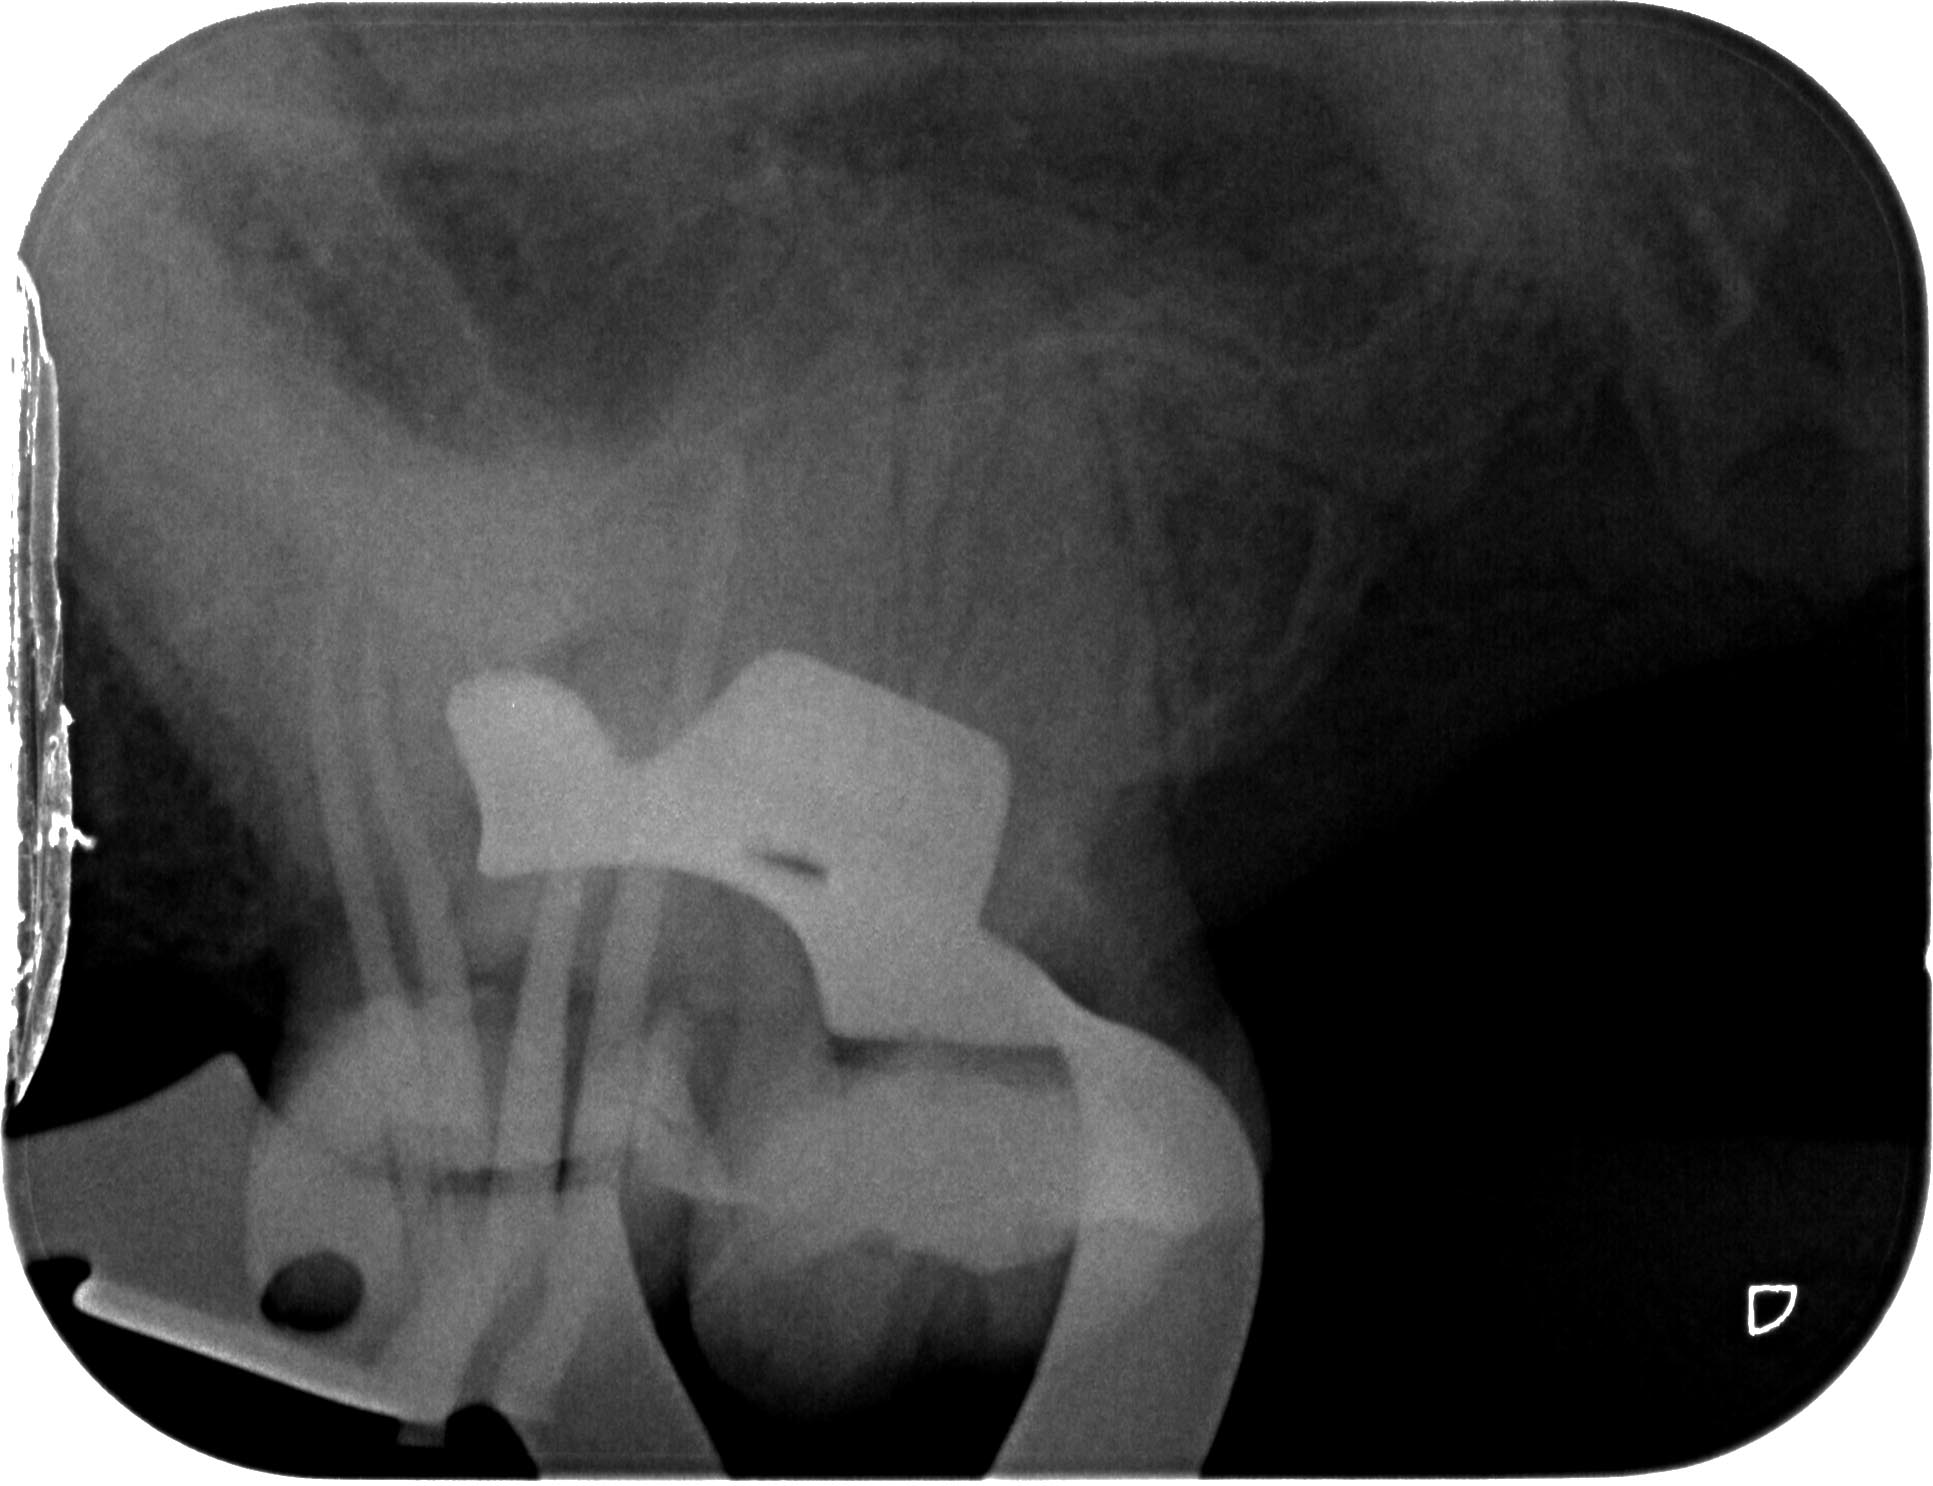

BN2627_1a-12 Veröffentlicht 1. Dezember 2014 am 1933 × 1486 in Unerwartete Anatomie Zahn 26, 27- die WF